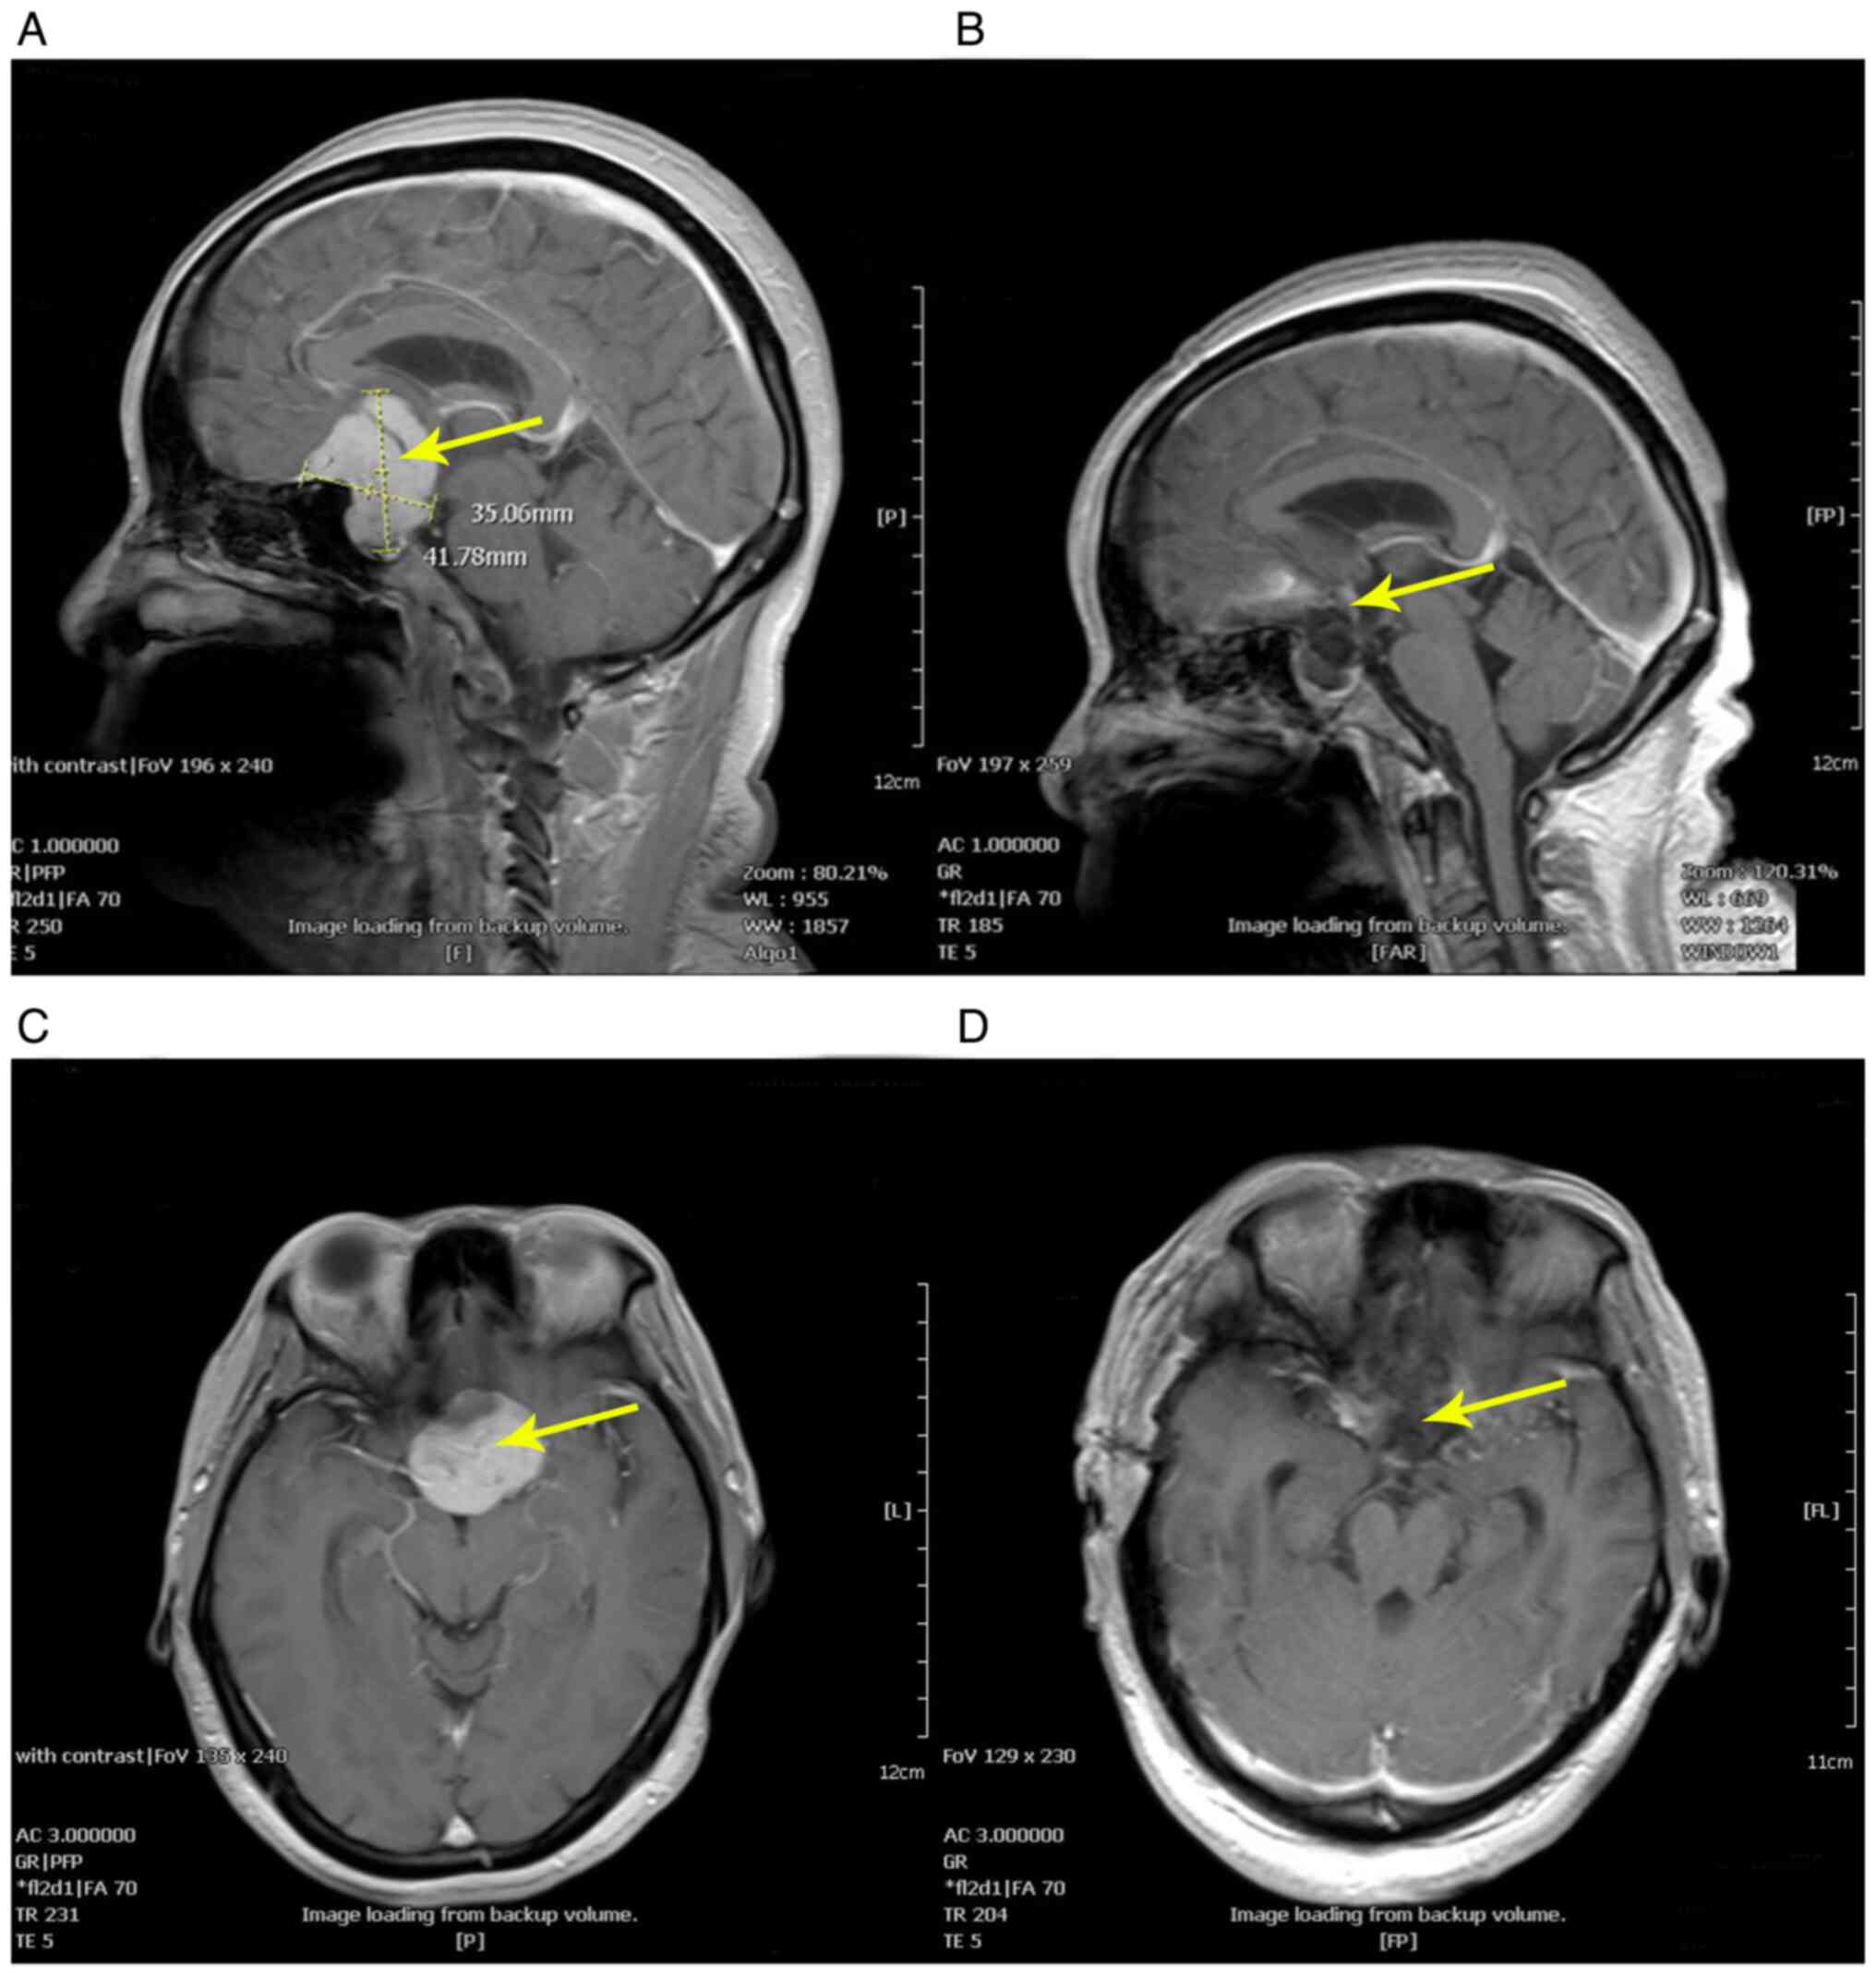

Case 2 of endoscopic supraorbital keyhole approach. Patient 4 is a 51-year-old female with decreased vision and headache. (A) Sagittal image of the preoperative MRI, showing an intrasellar tumorous lesion with a maximum diameter of 41.78 mm. (B) Sagittal image of the postoperative MRI, showing no remnant tumor tissue. (C) Axial image of the preoperative MRI. (D) Axial image of the postoperative MRI. The yellow arrow indicates the tumor or the tumor cavity.

The tumor diameter in the endoscopic supraorbital keyhole approach group ranged from 2.8-4.7 cm (mean, 3.4 cm), while the tumor diameter in the endoscopic extended transsphenoidal approach group ranged from 2.4-3.7 cm (mean, 2.8 cm). According to the postoperative pathological results, all cases were diagnosed as TSM (representative staining in Fig. 1). According to preoperative and postoperative cranial MRI images (Fig. 2, Fig. 3, Fig. 4 and Fig. 5), in the endoscopic supraorbital keyhole approach group, there were 16 cases (94.1%) that achieved GTR and only 1 case (5.9%) that achieved NTR. In the endoscopic extended transsphenoidal approach group, there were 18 cases (94.7%) that achieved GTR and only 1 case (5.3%) that achieved NTR. The postoperative visual acuity recovery showed that in the endoscopic supraorbital keyhole approach group, 23 eyes were improved, 8 eyes were maintained, 3 eyes deteriorated and the visual recovery was ~67.6%. In the endoscopic extended transsphenoidal approach group, 32 eyes were improved, 4 eyes were maintained, 2 eyes deteriorated and the visual recovery was ~84.2%. In the supraorbital keyhole approach group, there was no cerebrospinal fluid leakage, while in the extended transsphenoidal approach group, cerebrospinal fluid leakage occurred in 3 cases (15.8%). However, anosmia occurred in 1 case (5.9%) via the endoscopic supraorbital keyhole approach. No vascular injury, frontal lobe contusion or intracranial infection occurred in all cases. In these two groups, no tumor recurrence was found during the follow-up of ~5 years.